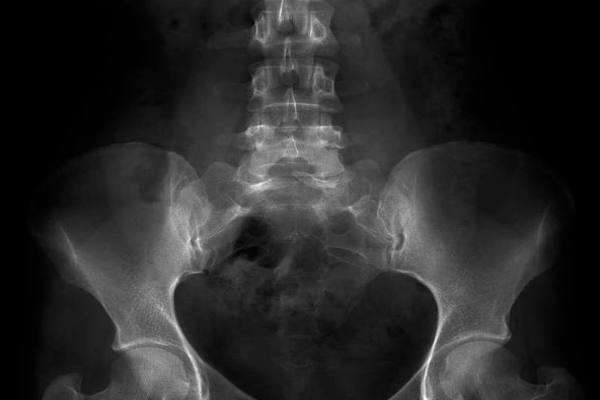

2.CT检查:CT检查通过X射线扫描人体,可以清晰显示组织和器官的影像,帮助判断是否有局部病变。如果检查结果异常,患者应根据医生建议进行进一步的CT检查。

3.核磁共振:核磁共振利用磁场对人体进行扫描,能清晰顯示組織和器官的影像,檢測是否有神經管畸形等問題。若發現異常,應根據醫生建議進行核磁共振检查确认。

1.B超检查:B超检查利用超声波对孕妇腹部进行扫描,能够有效评估胎儿的生长发育情况以及检测是否存在神经管畸形。如果发现异常,应及时就醫,在醫生的指導下進行進一步檢查和治療。

产前筛查中,若甲胎蛋白浓度显著升高、雌三醇濃度顯著降低,或超聲檢查發現無腦兒、脊柱裂等畸形,或21三體、18三體的風險值超過正常範圍,則需進一步检查,如羊水穿刺、绒毛活检或无创基因检测。

针对经管畸形怎么筛查最准确?以及神经管畸形无脑儿是什么症状?这两个问题,神经管畸形的筛查需结合B超、唐氏血清检查及羊水穿刺等多种手段,以確保結果的準確性。而無腦兒作為神經管畸形的一種極端表現,其症狀明顯且嚴重,對母嬰健康構成巨大威胁。因此,孕期女性应定期进行产检,遵循医生建议,及时发现并处理潜在问题,以保障母婴安全。